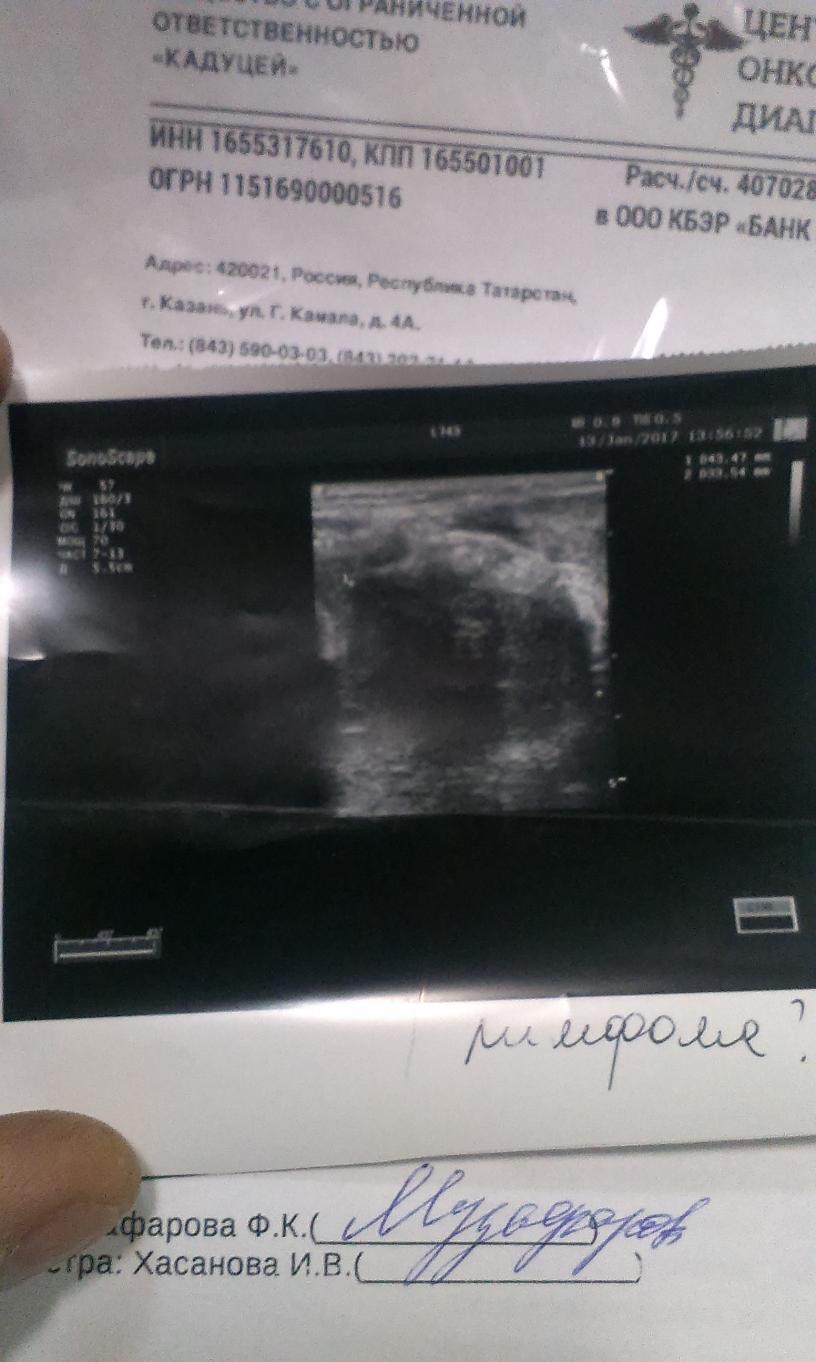

жидкость в плевральной полости не обнаружено при кт грудной клетки., но образование обемное есть и нечеткими контурами сказали, прям когда давишь на опухоль, боль прям по связкам поднимается в затылок., и кстати после употр***ения алкоголя, даж в небольшом количестве, начинает болеть голова

Миниатюры

Нажмите на изображение для увеличения

Название: IMAG0218.jpg

Просмотров: 589

Размер:	93.9 Кб

ID:	1576   Нажмите на изображение для увеличения

Название: IMAG0217.jpg

Просмотров: 712

Размер:	93.2 Кб

ID:	1577

Айрат, приветствую!! Размеры немалые образования- от него и кашель и боль в груди. Пункция это не очень-то информативно при лимфоме. Подмышечные ЛУ не прощупываются? Написано до 1,4 по кт..видимо в норме считают.. Хорошо что сделали - биопсия намного информативней пункции. Теперь надо подождать!